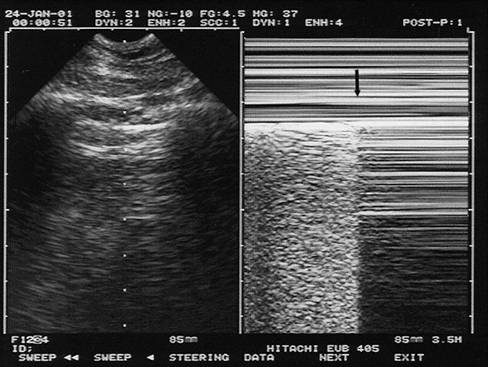

图15:肺部m型超声下"肺点"征象,提示气胸诊断(图片摘自annals of

sam征阳性M型超声图片

二尖瓣sam征M型示意图